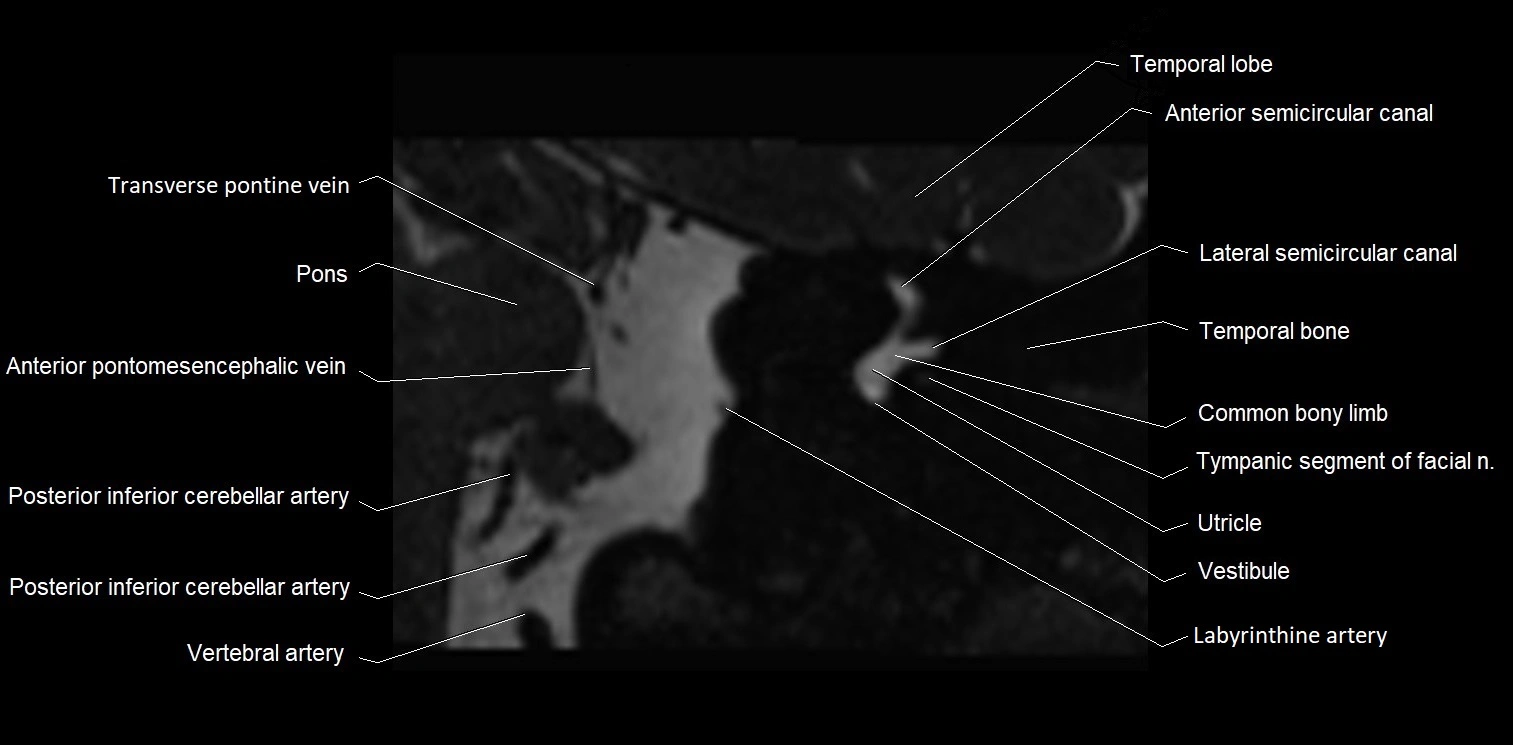

MRI Appearance

• The abducens nerve is a small, thin, linear structure

• Best visualized on high-resolution T2-weighted 3D MRI sequences (e.g., FIESTA or CISS)

• Seen as a hypointense (dark) line running from the brainstem at the pontomedullary junction, traversing the prepontine cistern, and entering Dorello’s canal under the petrosphenoidal ligament, then into the cavernous sinus, and finally the orbit

• May be challenging to visualize in standard MRI due to its small size

• Pathology may be inferred by absence, displacement, or enhancement of the nerve

MRI images

image